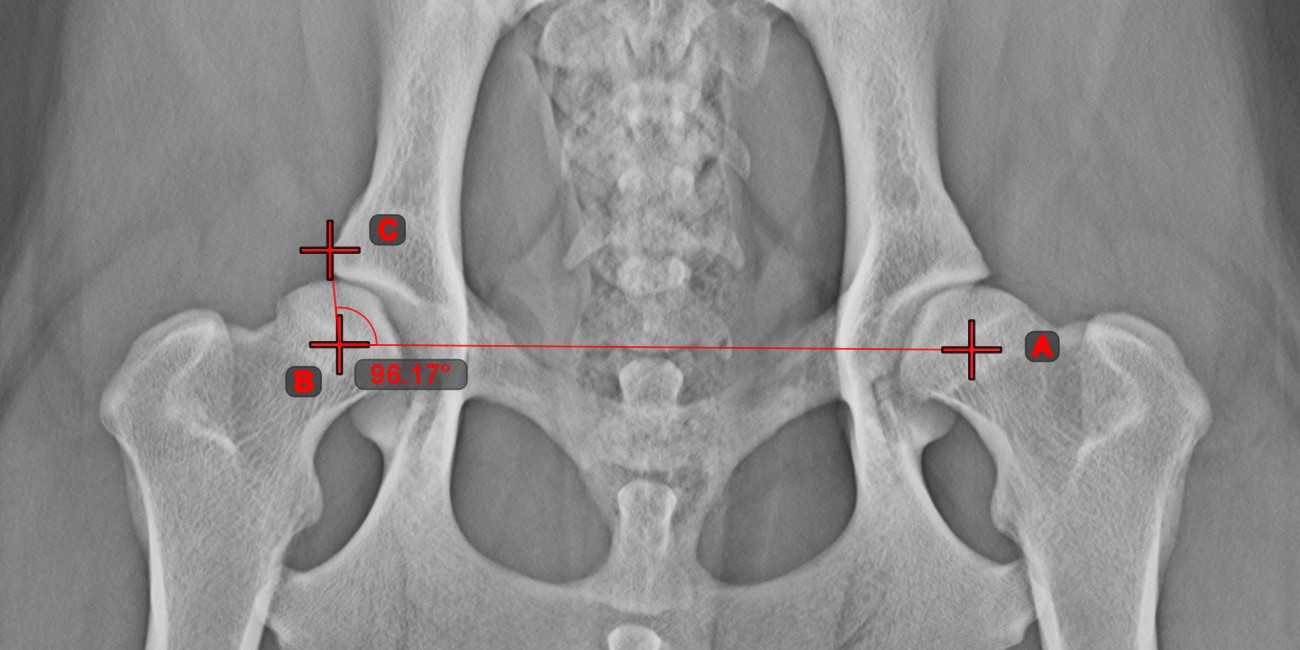

Angle from 3 Points

The Angle from 3 Points tool is a simple and effective way to calculate an angle from just three points.

Start by selecting the tool from the left toolbar and assign it to one of the available mouse buttons. Place the start point of the initial side, the vertex, and the end point of the terminal side of the angle, or select the points from the scene. The sides of the angle will be automatically constructed, thus calculating the angle between the lines.

Modify the position of the three points to change the arc of the angle by using the Select/Move Item tool.